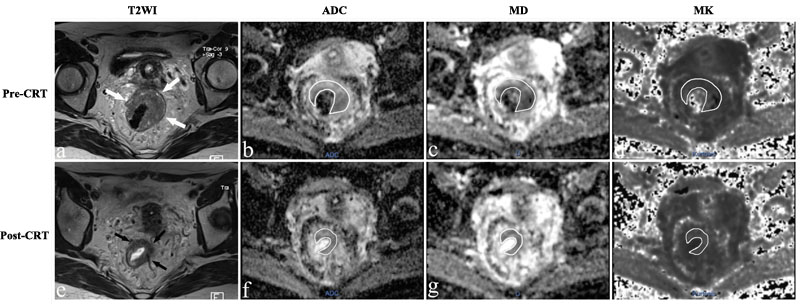

The population was consisting of 56 patients (16 females, 40 males) with an average age of 52.1±11.4 years. Fourteen patients showed pCR (Figure 1), whereas 42 patients were classified as non-pCR (Figure 2).

Figure 2: MR images of a 43-year-old woman with a non-pCR. a.-e. T2-weighted MR image before and after CRT shows that there is a visible tumor with a horseshoe shape in the rectum (arrows). The ADC, MD and MK values were 0.924×10-3 mm2/s, 1.424×10-3 mm2/s, and 0.876 before treatment. After CRT, the ADC and MD increased slightly to 0.947×10-3mm2/s and 1.533×10-3mm2/s, respectively, and the MK value decreased slightly to 0.812.